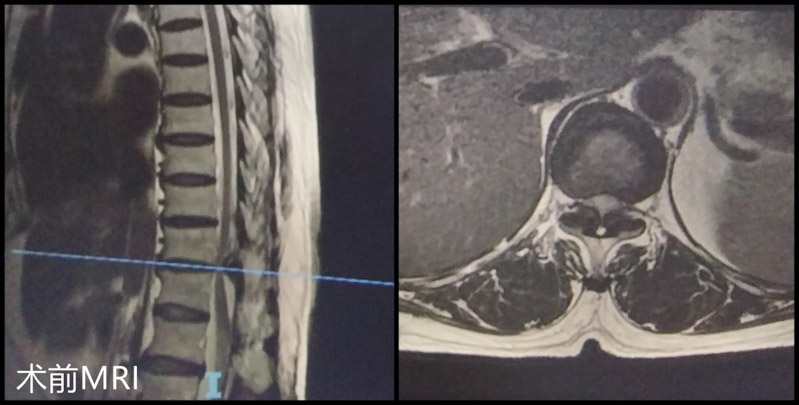

▲根據(jù)胸腰椎磁共振顯見T11/12黃韌帶骨化、T11/12脊髓變性、T11/12椎管狹窄嚴(yán)重

完善相關(guān)檢查后,柳州市人民醫(yī)院脊柱外科團(tuán)隊(duì)就患者的病情進(jìn)行了科內(nèi)討論,一致認(rèn)為患者已經(jīng)做過腰椎開放減壓融合內(nèi)固定手術(shù),但術(shù)后癥狀未緩解,考慮其目前癥狀為脊髓變性引起的黃韌帶骨化繼發(fā)胸椎管狹窄,需盡早手術(shù)解除脊髓壓迫。